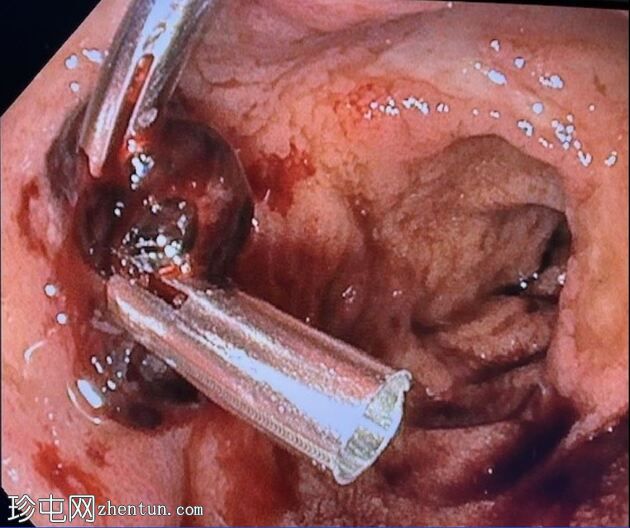

消化道内镜检查

8.jpeg

照片

十二指肠壁溃疡

食管炎

止血

及止血夹

胃底可见变质血液

内镜报告:

食管:LA C级食管炎。

胃:胃底可见变质血液及大血块。吸痰、冲洗并调整患者体位以移动血块后,未在胃底或胃体部发现病变。未发现活动性出血点。

胃窦:幽门前区可见三处溃疡,每处均小于1厘米,底部均清洁。

十二指肠:

D1:D1前壁可见一处含血块的溃疡。应用两个止血夹止血,并在溃疡周围注射1:10,000肾上腺素。

D2:D2可见两处溃疡。